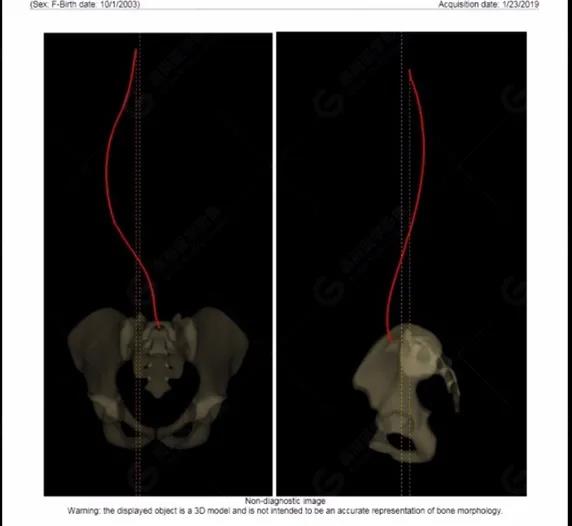

拍攝完畢后利用系統(tǒng)自帶的 Ster EOS 3D工作站對(duì)圖像進(jìn)行后處理,自動(dòng)生成臨床常用的參數(shù)值以及DICOM圖像,如圖所示:(2019-01-23)

脊柱側(cè)彎最重要一個(gè)臨床參數(shù)是側(cè)彎角(Cobb角),目前臨床公認(rèn)的Cobb角>10 °診斷為脊柱側(cè)彎;如Cobb角進(jìn)行性持續(xù)性增加>40 °需要手術(shù)矯正治療。

本例患者胸椎右側(cè)彎,Cobb角(T6/T12)為47°,遂行手術(shù)矯正治療。術(shù)后多次隨訪的Cobb角(T10/L3)為12°-15°之間,較術(shù)前明顯縮小。